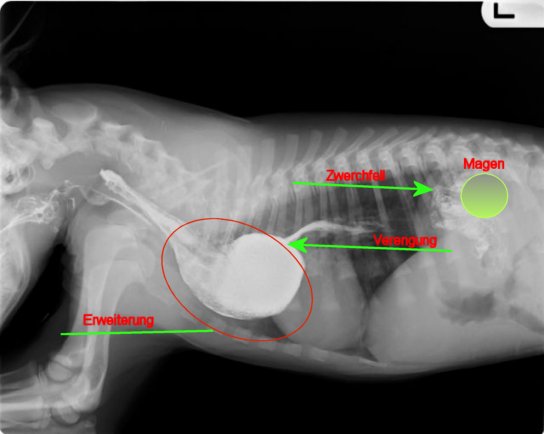

Auf dem Röntgenbild erkennt man deutlich die erweiterte Speiseröhre. Eigentlich ist die Speiseröhre in ihrem ganzen Verlauf gleichmäßig dick.